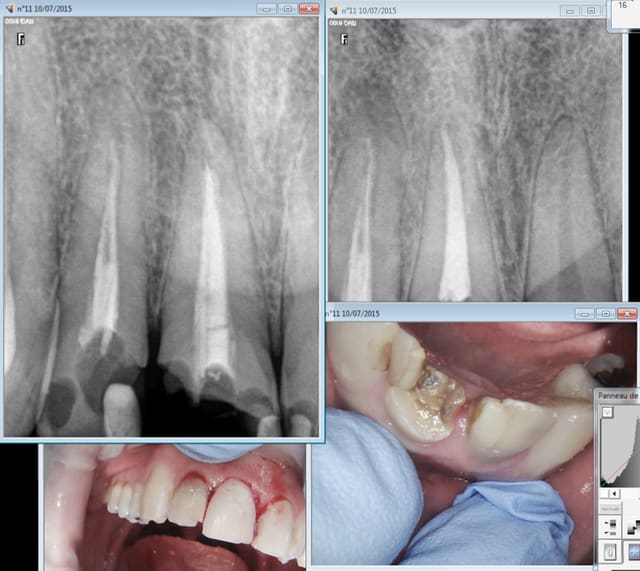

Ce type de traitement foireux c'est tous les jours que j'en vois aujourd'hui encore : bingo !

Capture d e cran 2015 07 10 20.01 - Eugenol